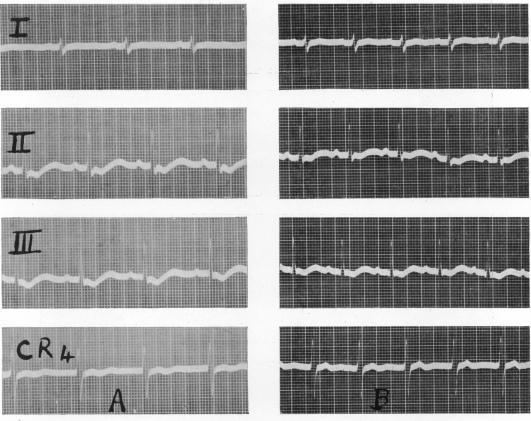

Ellis L B

Office of the Chief Surgeon, European Theatre of Operations, U.S. Army.

Br Heart J. 1946 Apr;8(2):53-61.